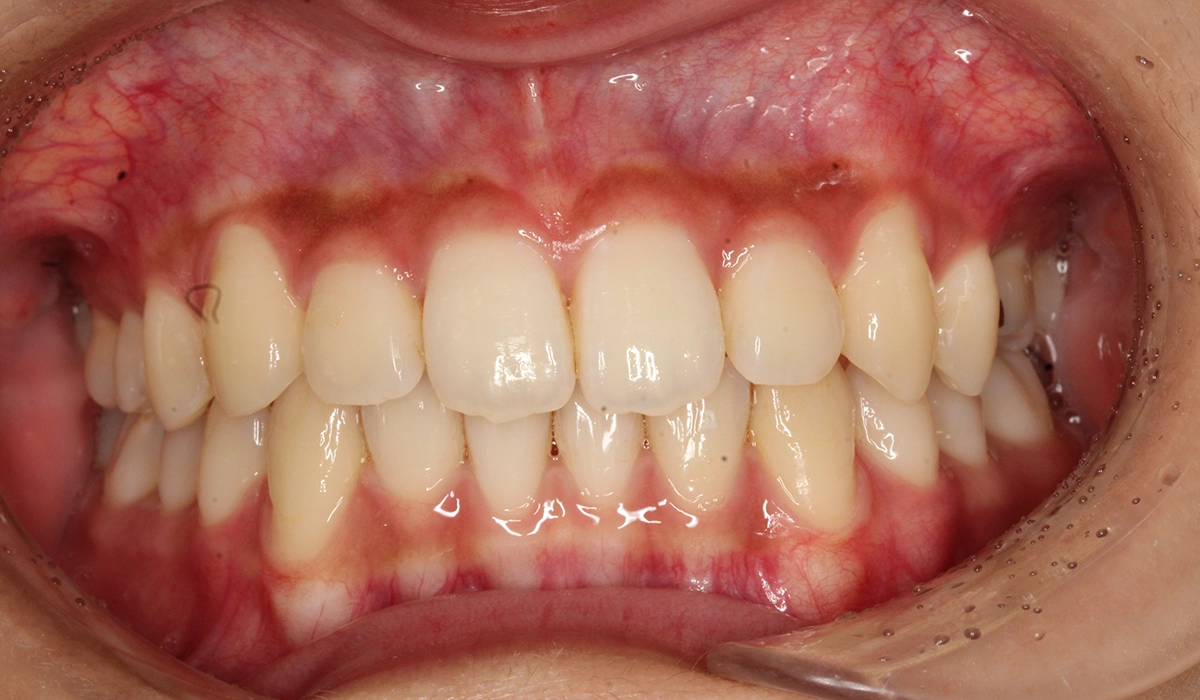

術前:正面